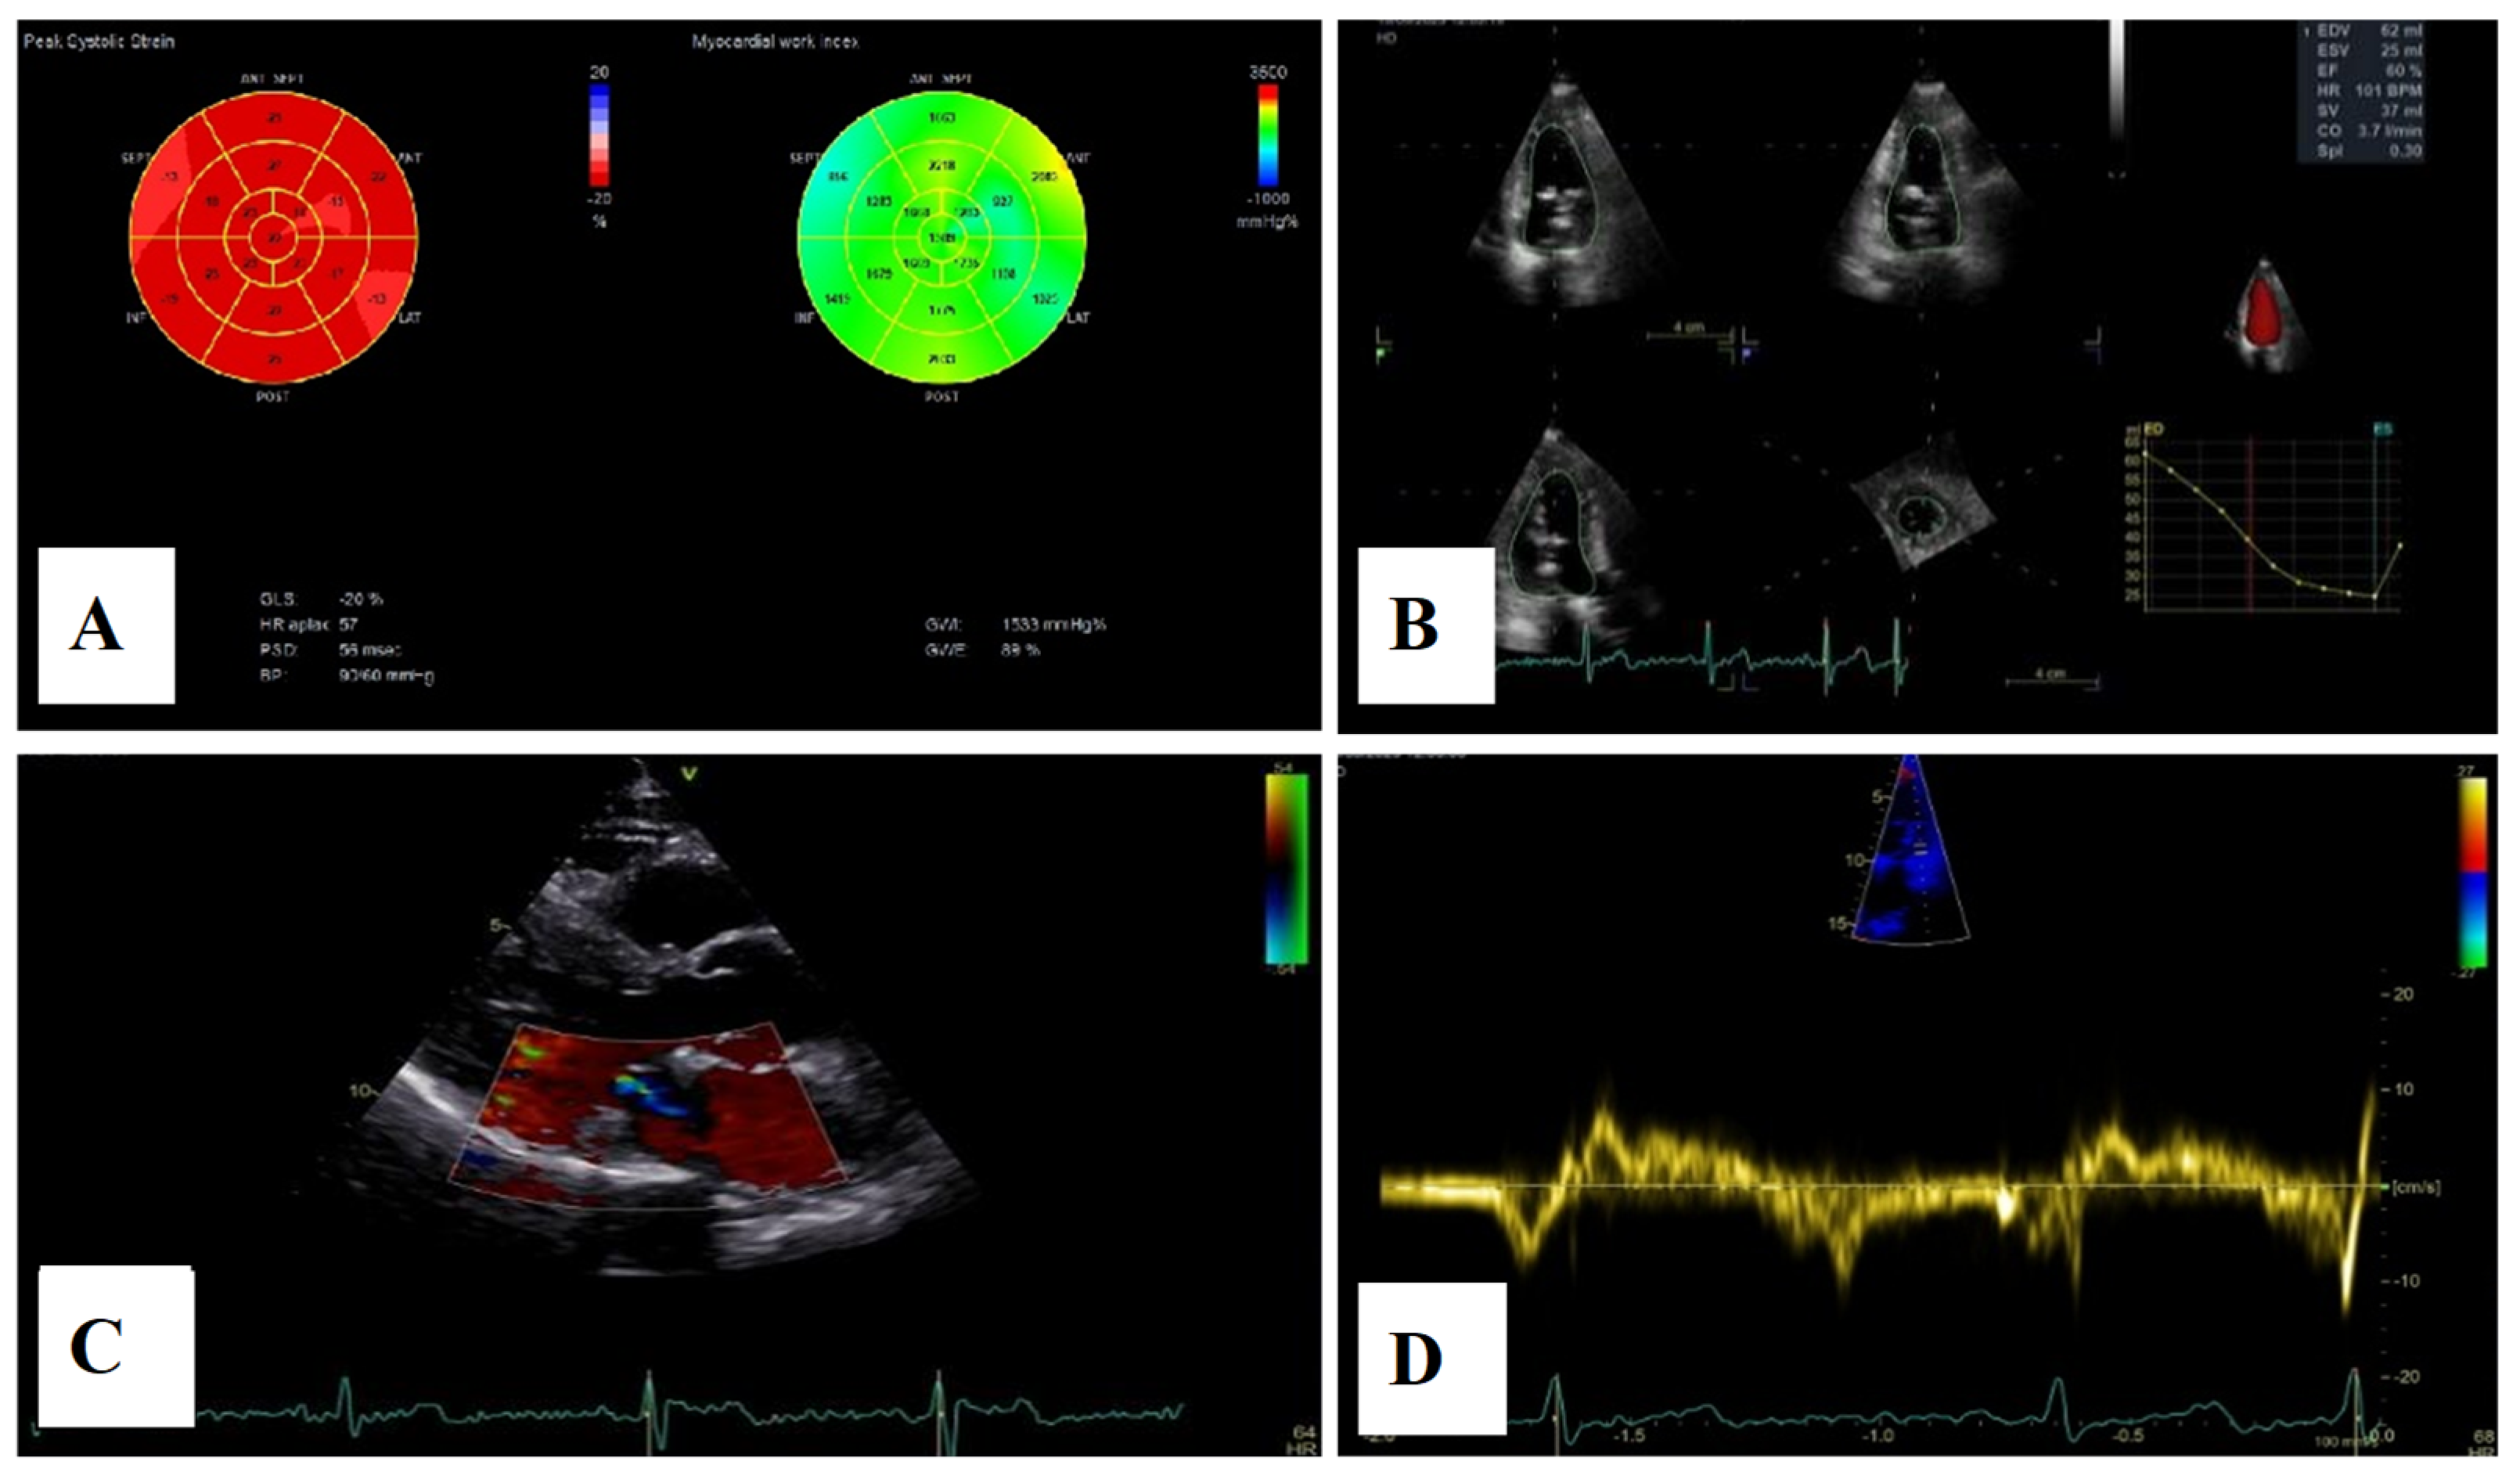

Transthoracic echocardiography revealed myxomatous degeneration of the mitral valve with bileaflet redundancy, increased leaflet length and thickness, and prolapse of both leaflets. Notably, a mitral annular disjunction (MAD) measuring 10 mm was observed in the parasternal long-axis view at end-systole (Figure 2A–C). Additionally, systolic “curling motion” of the posterolateral wall of the left ventricle was present, and the Pickelhaube sign was documented (Figure 3).

Figure 2.

Mitral valve prolapse with MAD on transthoracic echocardiography (TTE). (A)—TTE parasternal long-axis view in end-diastole displaying excessive leaflet length and thickness, (B)—TTE parasternal long-axis view in end-systole displaying mitral annular disjunction-MAD of 10 mm length (red arrow), and (C)—apical 4-chamber view displaying a displacement of both leaflets > 2 mm above the plane of the annulus.

Severe mitral regurgitation was identified, manifested by an eccentric regurgitant jet and associated left atrial dilatation (Figure 4). Moderate tricuspid regurgitation with right atrial dilatation was also present. Both the left and right ventricles were of normal size and function. Global longitudinal strain was preserved for both ventricles, with an average of −22.9% for the left ventricle and −22.0% for the right ventricle, although a mild degree of dispersion in longitudinal strain peaks was observed (Figure 5).

Figure 4.

Apical four chamber view showing severe mitral regurgitation with left atrial dilatation.

Figure 5.

2D speckle-tracking echocardiography used as a tool for assessing left ventricular systolic performance (GLS average −22.9%), with some degree of dispersion in longitudinal strain peaks.

For a comprehensive morphological and functional evaluation of the mitral valve, transesophageal echocardiography was performed. Three-dimensional imaging provided an “en face” view of the mitral leaflets, which confirmed the previous diagnosis of bileaflet mitral valve prolapse involving scallops A1, A2, A3 and P1, P2, P3. Severe mitral regurgitation and moderate tricuspid regurgitation were also documented (Figure 6A–D).

Figure 6.

(A,B)—Transoesophageal echocardiography (TEE) showing severe mitral regurgitation. (C,D)—TEE 3D view, displaying bileaflet prolapse and mitral annular enlargement. Mitral valve apparatus geometry and mitral valve dynamics were evaluated using EchoPAC software version BT12.